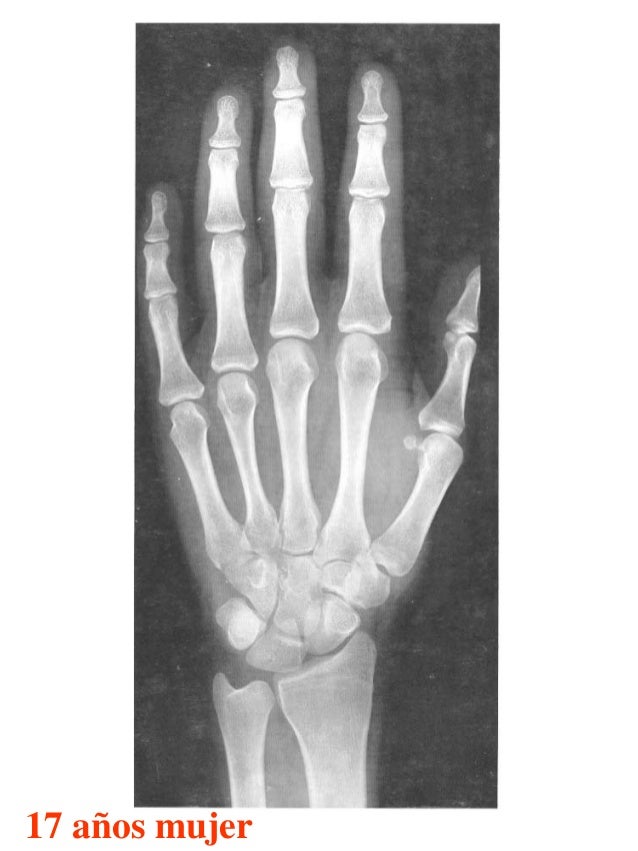

Tablas De Greulich Y Pyle The standards established by greulich and pyle, undoubtedly the most popular method, consist of two series of standard plates. The standards established by greulich and pyle, undoubtedly the most popular method, consist of two series of standard plates. El documento lista las edades. This systematic review summarizes the. The greulich and pyle method is one of the two main ways to assess the bone age of children. Both main methods of bone age. Scribd is the world's largest social reading and publishing site. 153 recomendaciones • 616,869 vistas. Atlas greulich y pyle | pdf | descarga gratuita. The greulich and pyle atlas is used to estimate the age of children and adolescents. The radiographic atlas of skeletal development of the hand and wrist by ww greulich and si pyle is a classic radiological.

Tablas De Greulich Y Pyle . Scribd is the world's largest social reading and publishing site. This systematic review summarizes the. The radiographic atlas of skeletal development of the hand and wrist by ww greulich and si pyle is a classic radiological. The standards established by greulich and pyle, undoubtedly the most popular method, consist of two series of standard plates. The greulich and pyle method is one of the two main ways to assess the bone age of children. El documento lista las edades. Both main methods of bone age. 153 recomendaciones • 616,869 vistas. Atlas greulich y pyle | pdf | descarga gratuita. The greulich and pyle atlas is used to estimate the age of children and adolescents.